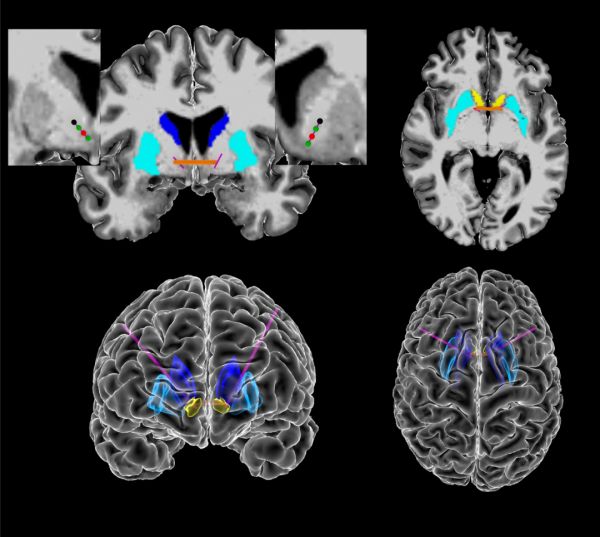

深部脑刺激的方式对于一些心理疾病的治疗具有不错的反馈效果,但是在治疗的过程中,深部脑刺激的频率与强度都是跟医生的经验相关,这也意味着这类治疗手段,对于医生的水平以及经验要求较高,具有较大的升级空间。近日,一项有关用AI的研究分析首次识别出了大脑中强迫症相关的脑电波信号,为强迫症的诊断和针对性治疗带来新的增益。

对于强迫症患者来说,深部脑刺激的频率与强度跟医生的经验水平挂钩,疾病的治疗管理非结构化,管理比较复杂,精准刺激深部脑电部位,识别患者强迫症的发作时机成为机器干预的关键环节。

运用AI技术识别大脑中强迫症相关的脑电波信号,针对这一信号调整深度脑刺激强度,为强迫症的针对性与精准治疗打开了新窗。

这个研究团队来自美国布朗大学脑科学研究所,David A. Borton 教授带领的研究团队通过对 5 名重度强迫症患者进行长期脑电监测,经过长期的收集研究与观察,利用人工智能对患者生活中的强迫行为进行分析,评估患者各种微妙的情绪变化,并与脑电波活动相匹配。除了脑电波信号,研究人员还收集了一套强迫症患者行为的生物标志物,包括面部表情和身体运动。通过人工智能,他们发现这些行为和特征与大脑内部信号变化密切相关。

并且,研究人员也用试验证明了,当患者出现这些强迫症状,依据AI给出的深部脑刺激位置,可以显著地改善患者的强迫症状。研究人员也在不断地精进深部脑刺激的系统,向自动化刺激的方向前行。

什么意思呢?就是在患者出现强迫症信号的时候,系统可自动捕捉并及时利用深部脑刺激进行针对性缓解,依据患者症状强度,自动调节刺激强度。目前研究人员计划进一步招募更多患者进行试验,以捕捉更多的强迫症脑电信号标志,丰富自动化深部脑刺激系统的功能。目前研究人员正在开发自动化深部脑刺激系统。